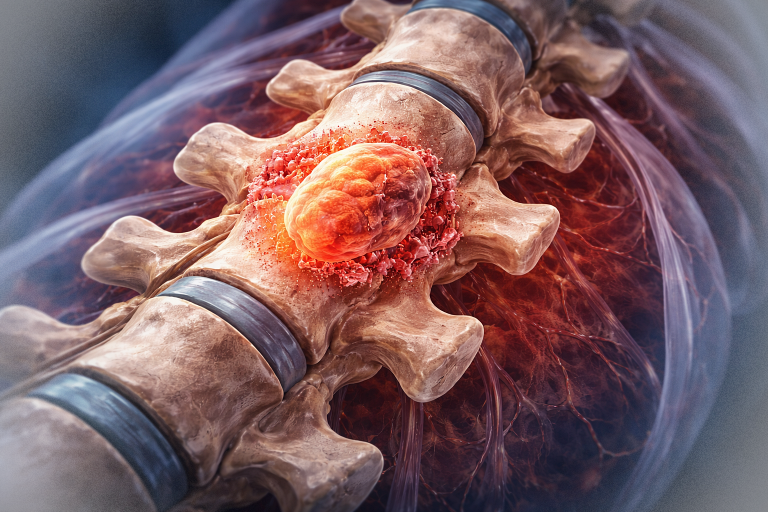

B. Condrosarcomul

Tumoră malignă ce derivă din țesut cartilaginos.

Frecvent localizat la baza craniului (clivus, sfenoid).

Simptome: cefalee, diplopie, afectarea nervilor cranieni.

Creștere lentă, dar invazivă.

Tratament: excizie chirurgicală completă + radioterapie postoperatorie.

C. Cordomul

Tumoră rară, malignă, ce derivă din resturi embrionare ale notocordului.

Apare frecvent la nivelul clivusului (baza craniului).

Se dezvoltă lent, dar are potențial invaziv.

Simptome: durere, pareze oculomotorii, tulburări de deglutiție.

Tratament: rezecție chirurgicală maximală + radioterapie stereotactică – protonoterapia sau radioterapia cu ioni de carbon.